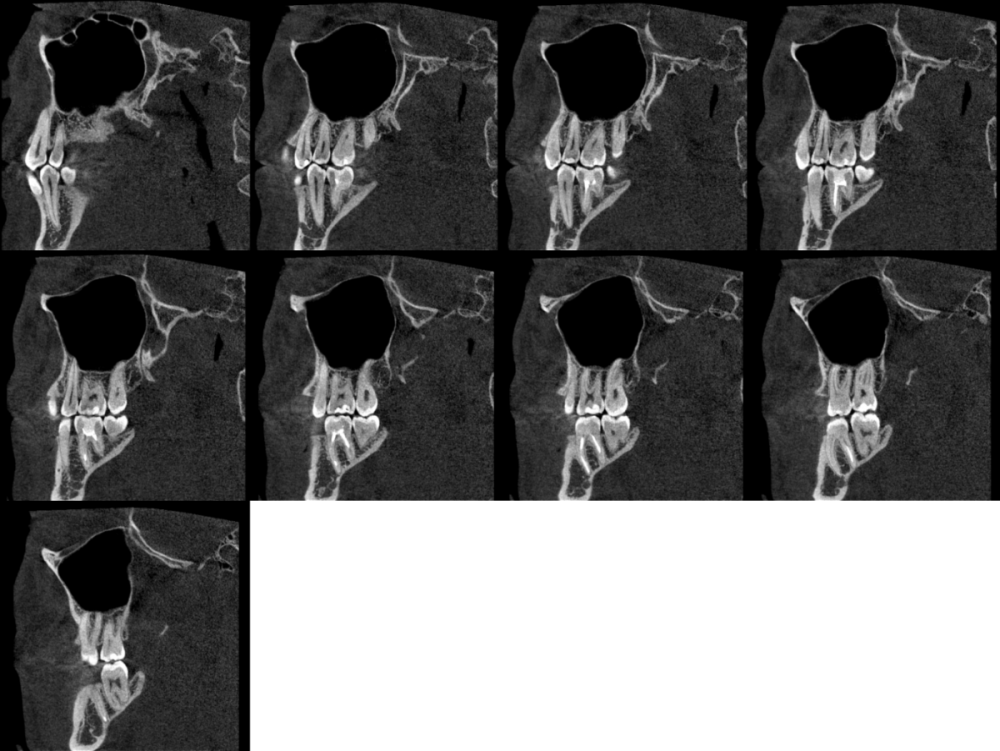

podivilov Опубликовано 14 января, 2024 Поделиться Опубликовано 14 января, 2024 (изменено) На этой неделе лечил два зуба — нижнюю шестёрку с левой стороны и нижнюю шестёрку с правой стороны. Левая шестёрка успешно вылечена, ничего не болит. С правой же проблемы. Лечение правой шестёрки начали в эту среду, закончили лечение в пятницу. Всего было два приёма. После первого приёма, когда поставили временную пломбу с лекарством, зуб начал ныть — да так, что ночью несколько раз просыпался. Тогда нерв ещё не был удалён, поэтому я просто сообщил об этом лечащему стоматологу, — сказали, что всё нормально. В пятницу после завершения лечения думал, что всё, больше болеть не будет — болеть ведь нечему, нерв удалён и каналы запломбированы. Лечили за два приёма, последний приём длился два с половиной часа. После того, как отошла заморозка, действительно ничего не болело. Порадоваться этому успел ровно до ночи: к этому моменту ноющая боль вернулась. Думал, что так и должно быть, и просто лёг спать. В итоге и вчера, и сегодня ноющая боль сохраняется. Причём достаточно интенсивная — не слабая. Сильнее, чем была до лечения зуба. Острой боли нет, даже если нажимать на зуб. Боль усиливается ближе к ночи. Иногда кажется, будто ноет также верхний зуб на той же стороне челюсти. На сладкое и холодное зубы не реагируют, просто в течение дня сохраняется сильная ноющая боль. Почему-то не помогают даже обезболивающие — пробовал «Нурофен» и «Кетанов», но какого-то особого эффекта не ощутил. Был сегодня на приёме у другого стоматолога, где мне сделали КЛКТ снимок. На снимке ничего страшного не обнаружили — сказали, что корни запломбированы хорошо. Стоматолог сказал, что может распломбировать зуб и запломбировать заново, но предупредил, что боли могут пройти сами, и, вероятно, нет смысла сейчас что-либо делать. Загрузил на Google Drive КЛКТ снимок, сделанный сегодня (с просмотровщиком Planmeca Romexis): https://drive.google.com/file/d/1t5zrJj8r3p1SG44UCOw2RGo5PJQxerh4/view?usp=sharing Изменено 14 января, 2024 пользователем podivilov Дополнение Ссылка на комментарий

wladdX Опубликовано 14 января, 2024 Поделиться Опубликовано 14 января, 2024 Корневые каналы заполнены адекватно, на мой взгляд Ссылка на комментарий